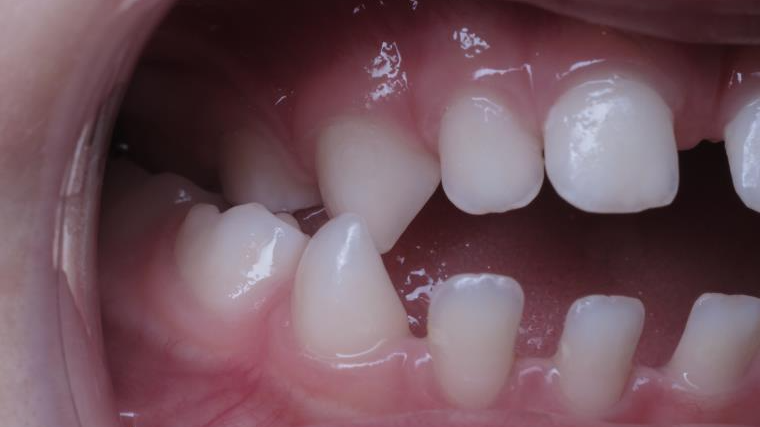

appareillage mobile pendant 3 ans

sectionnel multibagues pendant 8 mois

surveillance évolution de la dentition